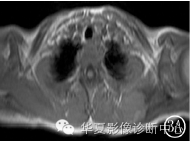

MR片(图3A~3C)示:左侧肩胛骨区呈膨胀性不规则的混杂信号,T1呈低信号,低层局部见略高信号,T2呈高信号,低层呈相对低信号,可见“液‐液”平面;肿块边界清楚,其内可见长T1、短T2的分隔,增强扫描病灶内分隔明显强化。

图3A MRIT1WI:左肩胛骨呈低信号影,液‐液平面不明显 图3B MRIT2WI:左肩胛骨病灶呈明显液‐液平面,上层高信号,下层低信号,其内见分隔 图3C MRI增强扫描:左肩胛骨病灶分隔明显强化